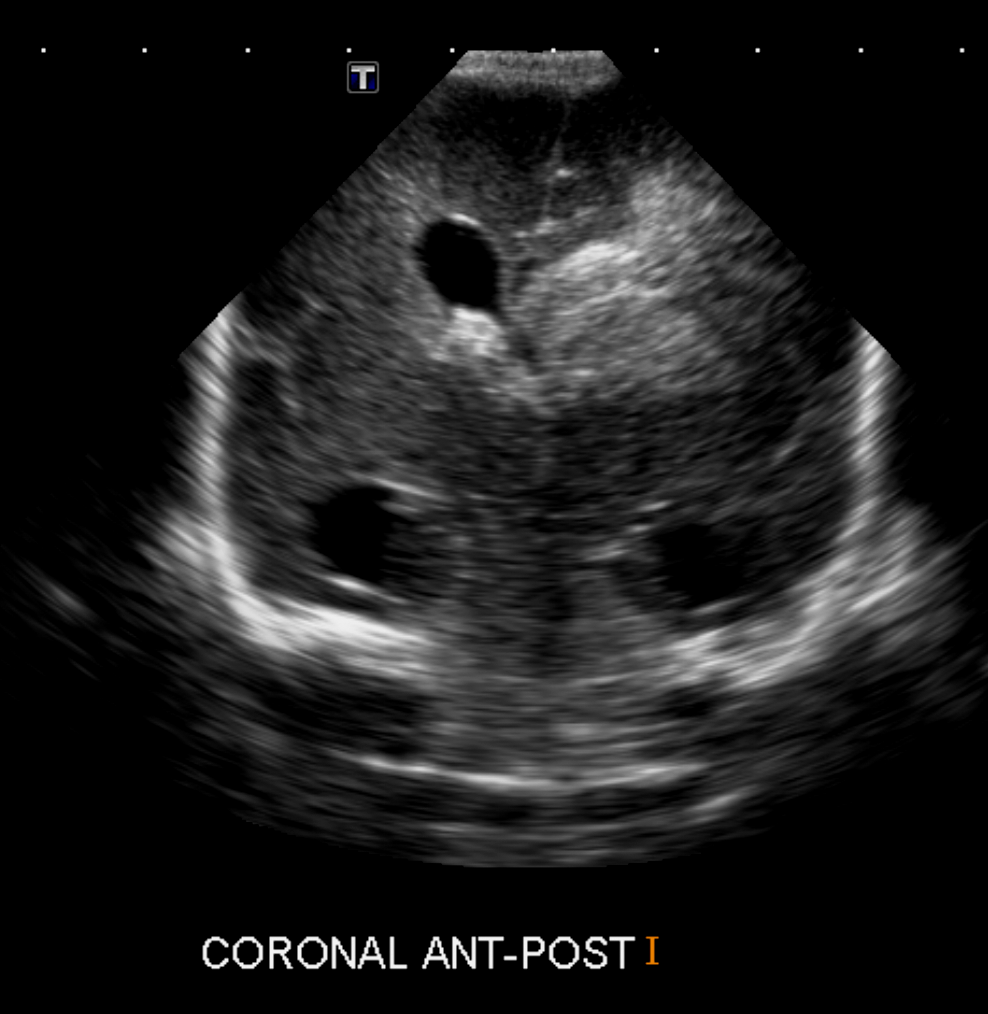

CSF spaces/ventricular system

There is prominence of the ventricular system. [Yes/No]

The choroid plexus is bulky/lobulated. [Yes/No]

There is a choroid plexus cyst measuring… [Yes/No]

There are debris/clots in the occipital horn. [Yes/No]

There is a posterior fossa cyst measuring… [Yes/No]

The tentorium is elevated/depressed. [Yes/No]

The lateral ventricle/s are dilated. [Yes/No]

There are pseudo cysts. [Yes/No]